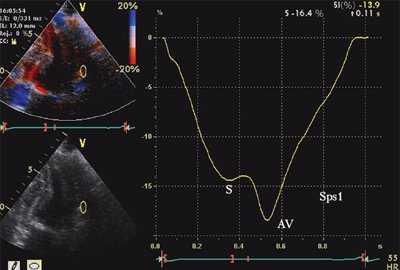

ЭхоКГ (стандартная и в режиме тканевой допплерографии) проводилась на ультразвуковой диагностической системе Vivid Five фирмы General Electric (США) секторным датчиком c частотой 3,75 МГц. Исследовалось движение продольных волокон миокарда в проекциях по длинной оси левого желудочка из верхушечного доступа. Тканевая допплерография проводилась в 4-, 3- и 2-камерной проекциях в каждом из 16 сегментов левого желудочка и в 4 точках митрального кольца: у основания заднеперегородочной, боковой, нижней и передней стенок левого желудочка. Оценивались следующие параметры.

- Амплитуда постсистолического пика скорости, регистрируемого в фазу изоволюмического расслабления (Sps). Вычислялось отношение скоростей Sps/Sm.

![Тканевая допплерография в норме. У больного с постинфарктным кардиосклерозом регистрируется высокоамплитудный пик постсистолической скорости (Sps)]()

б) При постинфарктном кардиосклерозе. У больного с регистрируется высокоамплитудный пик постсистолической скорости (Sps).

Вертикальная линия (AV) на рис. 3-5 соответствует времени закрытия аортального клапана. На представленных графиках также отмечается наличие базально-верхушечного градиента (снижение пиковых миокардиальных скоростей, продольного систолического смещения и деформации от основания к верхушке левого желудочка).